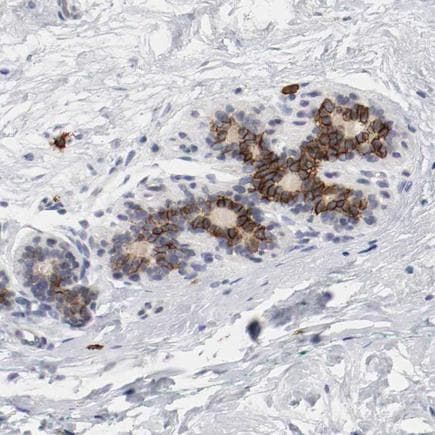

Anti-c-Kit antibody(ab260048)

Rabbit Polyclonal c-Kit antibody. Suitable for IHC-P and reacts with Human samples. Immunogen corresponding to Recombinant Fragment Protein within Human KIT aa 50-200.

Applications IHC-P

Species Reactivity Human